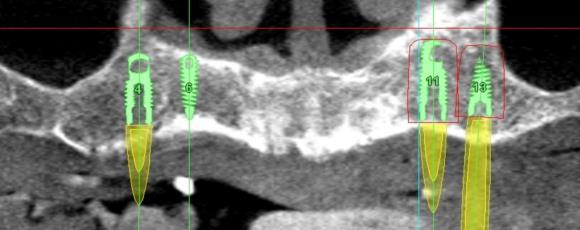

Compare a CBCT taken in 2011 vs in 2015, is there a difference? When is a good time to get a scan? A CBCT Scan is no longer a priviledge but it is a must diagnostic tool in Implant Dentistry. It gives you 3 dimesional view of a site, allows you to estimate proximity of vital structures such as a nerve or a sinus, you can study the anatomy, you can virtually plan a case, with or without a surgical guide.

Saying that scan is not necessary will soon be like stating xray is not essential. New CBCT machines deliver low dosage, fast scans for every clinical need..